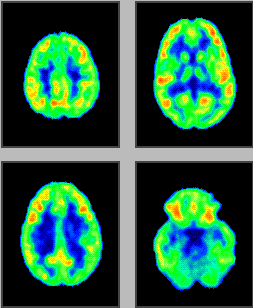

Language Processing

• Unpracticed Task

• Yellow and red regions are "hotter – higher cell activity

• Patient was unpracticed at the language learning task.

• The highest brain activities in the temporal lobe responsible for the hearing perception

• Prefrontal cortex responsible for understanding language.

• Practiced Task

• Same individual has now learned the language task and is spelling out.

• Concentrated in the Broca area of the cortex which is responsible for the motor control of voice

• Real-time image of brain function.